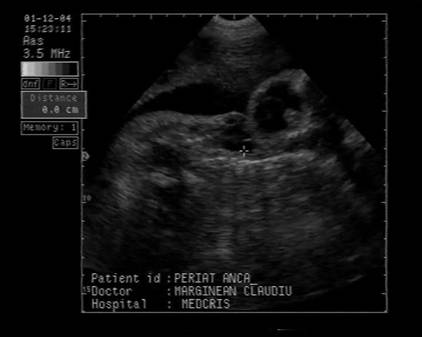

Fig . nr. 248. Chist de plex choroid , unilateral, la o sarcina de 17 sapt.